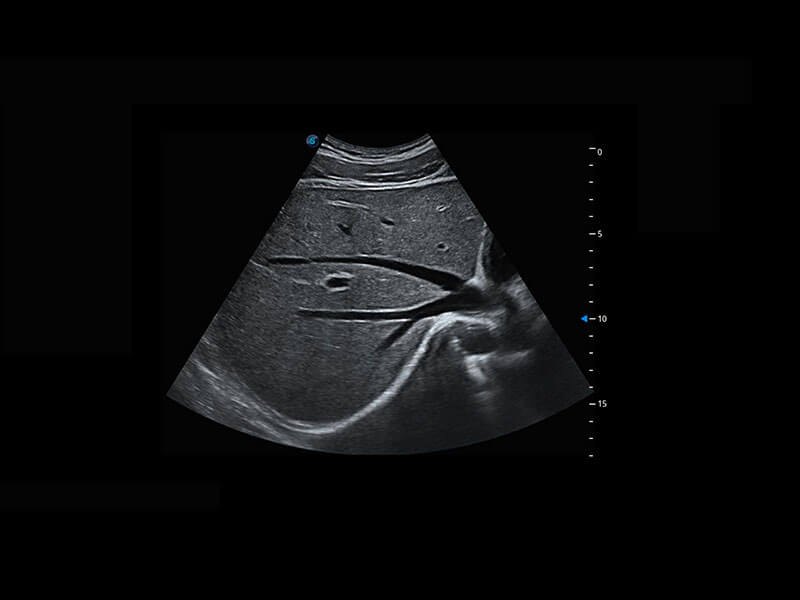

腔内妇科-宫腔分离

腔内妇科-卵巢